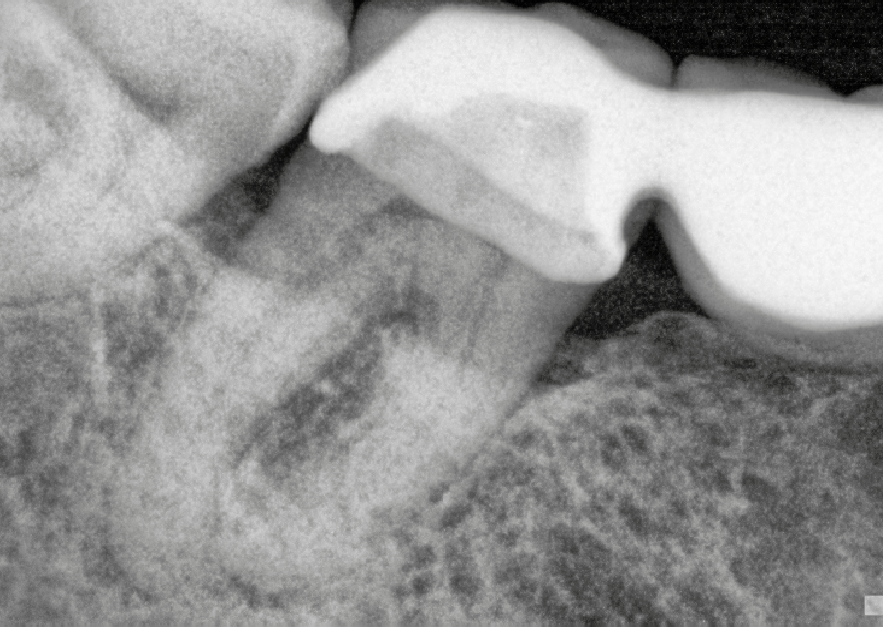

This lady attended for a new patient examination. Radiographs showed recurrent caries and an asymptomatic periapical area at 47 (the lower right second molar, bridge retainer).

Pre-operative radiograph